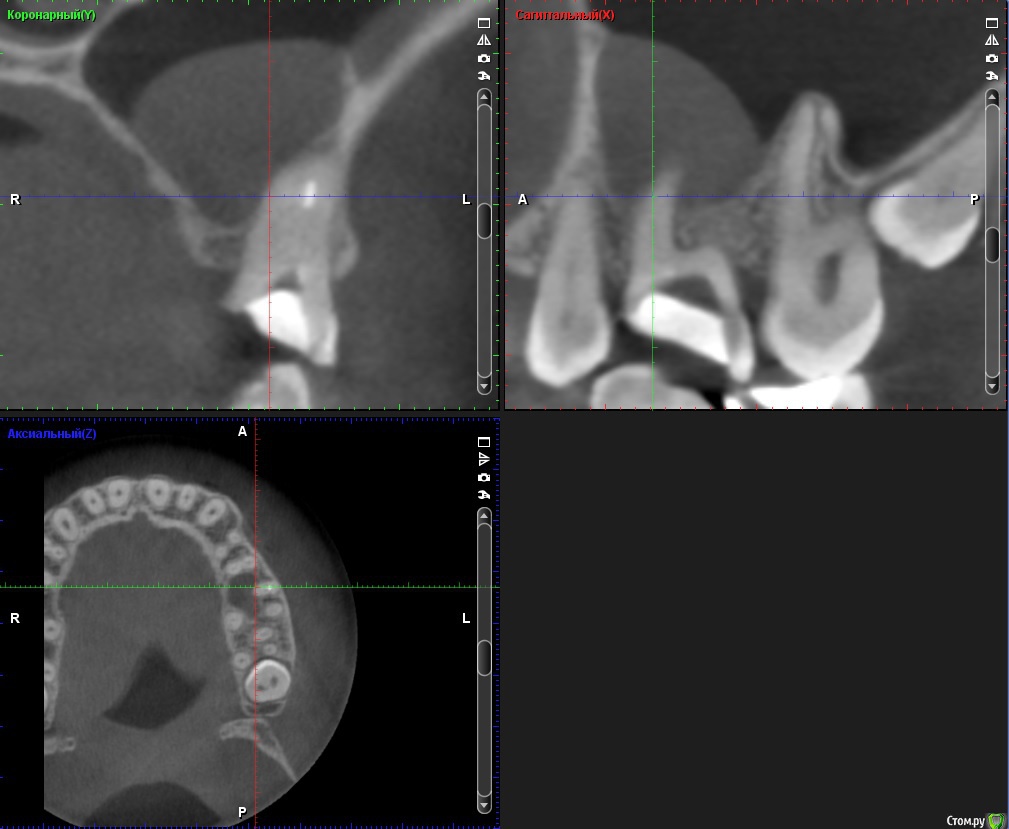

ClayMixer Опубликовано 18 ноября, 2016 Поделиться Опубликовано 18 ноября, 2016 (изменено) Здравствуйте! Вопросы по двум зубам (36 и 26): 1. Киста (36-ой зуб).Консультировалась у нескольких врачей. Мнения разные. От "можно поставить вкладку и коронку на n-ное количество времени до удаления; эту кисту не вылечить", до: "только удаление, желательно быстрее". 1) Можно ли вылечить этот зуб? И каков процент успеха?2) Есть ли смысл лечить зуб и ставить вкладку и коронку или лучше удалить и делать имплант? После того, как 36 зуб подготовили под вкладку - бывали неприятные непонятные ощущения (похожие на импульсы), не острые (длительностью 3 нед.) Вроде после этого времени стали утихать понемногу. 2. Инородное тело (обломок инструмента) в 26-м зубе.Врачи пытались извлечь его (без микроскопа) - безуспешно. Канал, в котором "застрял" инструмент не до конца "пройден".Критично ли это? Какова вероятность воспаления? (теперь патологический страх появления кисты ) Теоретически можно ставить вкладку и коронку? Ходила таким трансформером больше 5-ти лет, не беспокоил вообще. После попыток врачей достать инструмент также бывали неприятные непонятные ощущения (похожие на импульсы), не острые (длительностью 3 нед.) Вроде после этого времени стали утихать. При простукивании коронки обеих зубов болевых ощущений вроде не наблюдалось. Результаты КТ https://cloud.mail.ru/public/Fhy4/ESmeyU9hp Изменено 18 ноября, 2016 пользователем ClayMixer Ссылка на комментарий

ClayMixer Опубликовано 18 ноября, 2016 Автор Поделиться Опубликовано 18 ноября, 2016 26-ой зуб Ссылка на комментарий